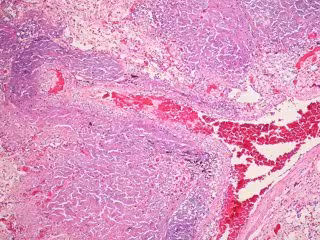

FLICKER/ PULMONARY PATHOLOGY

La tuberculosis afecta normalmente a los pulmones, si bien la bacteria la origina suele desarrollarse tan solo en las personas que tienen un sistema inmunológico debilitado.